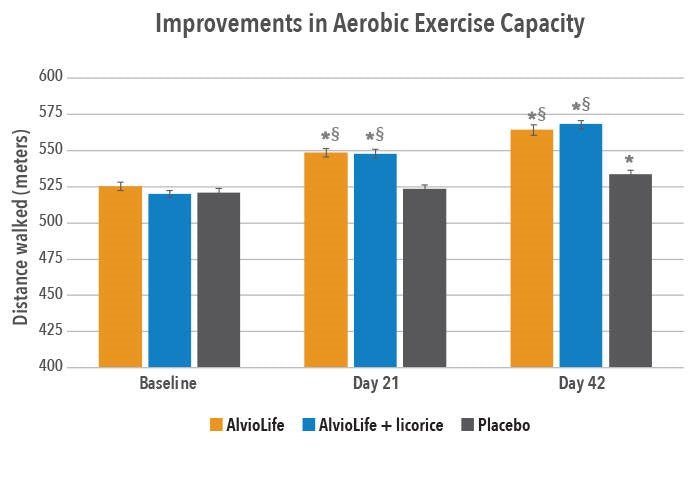

Etude clinique sur AlvioLife® pour le confort respiratoire – Revue internationale des sciences médicales (2021)

Évaluation de l’extrait combiné Boswellia-Aegle sur la fonction pulmonaire (VEMS/FVC) – Journal respiratoire clinique (2020)